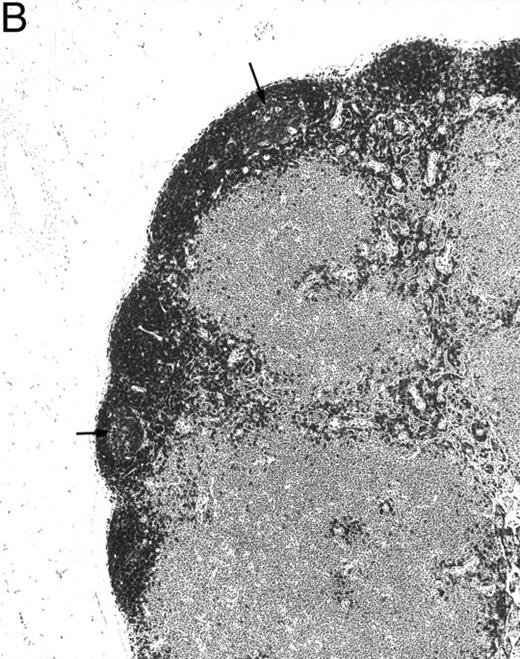

Histologic alterations occur in hematopoietic tissues of IFN-γ transgenic mice.Focal granulomatous lesions were seen in the bone marrow of many of the transgenic mice (Fig 4A) but not in control mice. These lesions were found to contain primarily Mac-2+ mononuclear cells (data not shown). In addition, the marrow cavities of IFN-γ transgenic mice contained residual degenerated cartilaginous masses in the metadiaphyseal (young) or diaphyseal (adult) parts primarily in long bones and ribs (Fig 4B). Moribund transgenic mice often had generalized or local secondary bacterial infectious lesions, including pyelonephritis, meningoencephalitis, endocarditis, bone marrow necrosis, arthritis, and uterine granulomas. Bacteria and bacterial colonies were often seen within the lesions.

Bone marrow alterations in IFN-γ transgenic mice. (A) Tibial bone marrow of a 3-month-old transgenic mouse showing granulomatous lesions (arrows) stained with H&E. The focal lesions were composed of clusters of histiocytes/macrophages (original magnification × 300; Bouin's fixed and paraffin-embedded section). (B) A rib of an 8-month-old transgenic mouse showing a cartilaginous mass in the marrow cavity attached to the cortical bone. Chondrocytes in the mass are degenerative. The mass is covered with a thin osseous layer. (Original magnification × 75; H&E; Bouin's fixed and paraffin-embedded section.)

Gross examination of animals at all ages studied showed that transgenic mice had much smaller spleens than those of normal littermates. Histologically, the white pulp areas in the spleens of transgenic mice were composed only of the periarteriolar lymphocytic sheaths (PALS), whereas the primary follicles and outermost marginal zones that typically contain B cells and surround the PALS were absent (Fig 5).

Spleen of a 6-month-old transgenic (A) and an age-matched control (B) mouse. White pulp of the transgenic mouse is composed only of lymphocytes in the PALS (arrows), whereas those areas in control mice are composed of primary follicle (f ) and marginal zone (m). (Original magnification × 75; H&E; Bouin's fixed and paraffin-embedded section.)